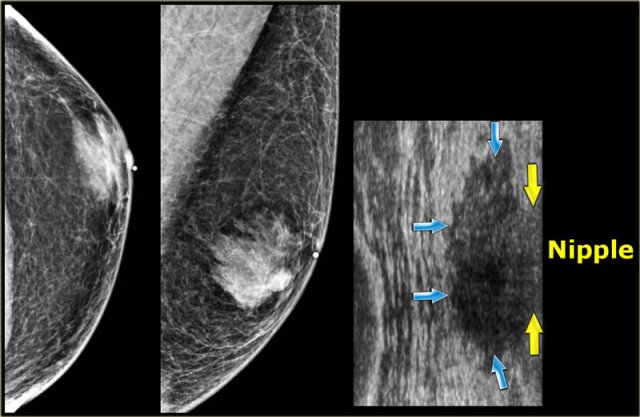

Mammogran and rotated ultrasound image Mammogran and rotated ultrasound image

Nodular pattern

The nodular pattern of gynecomastia is seen in the florid early phase.

It begins as an increased number of ducts and epithelial proliferation with edema and cellular fibroblastic stroma.

This phase is reversible.

On the left a mammogram and an ultrasound image of a patient with a nodular glandular pattern of gynecomastia.

Notice that it is situated underneath the nipple.

The ultrasound image shows the typical appearance of gynecomastia: a hypoechoic mass with lobulation or even spiculation.

If this was seen in a woman, you would say that this is a mass with microlobulation and spiculation, i.e. Birads IV or V.

In a man this is typical for gynecomastia.

On the left the same ultrasound image, but now in the normal position.

Notice how 'malignant' it looks.